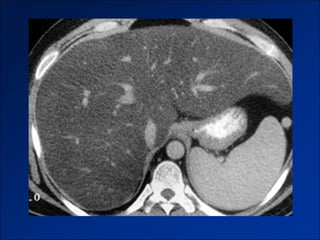

Hình ảnh trên CLVT

- Teo gan ở ngoại vi.

- Phì đại thùy gan trung tâm - phân thùy đuôi.

- Tuần hoàn bàng hệ qua hệ cửa.

- Huyết khối TM cửa – TM dẫn lưu.

- Các shunt mạch máu trong gan.

Figure 4a. Large regenerative nodules in a 27-year-old woman with chronic (2 years) Budd-Chiari

syndrome.

©2002 by Radiological Society of North America   Brancatelli G et al. Radiographics 2002;22:847-862